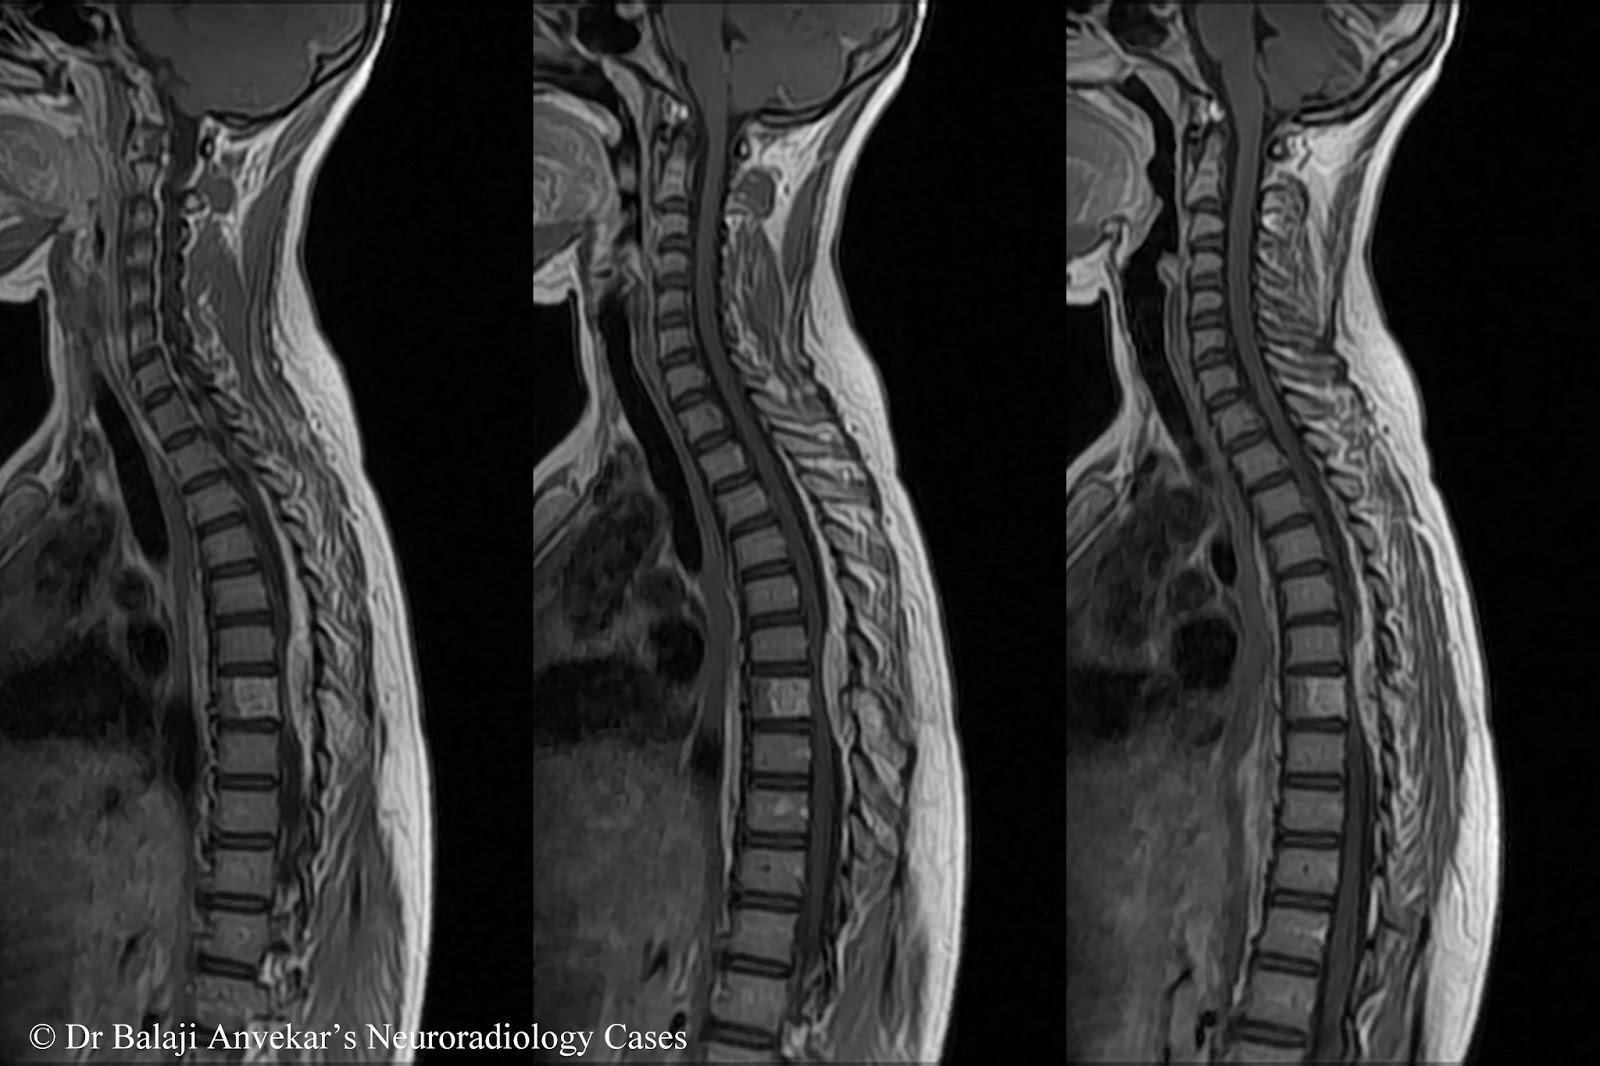

Что такое эпендимома спинного мозга: симптомы и лечение